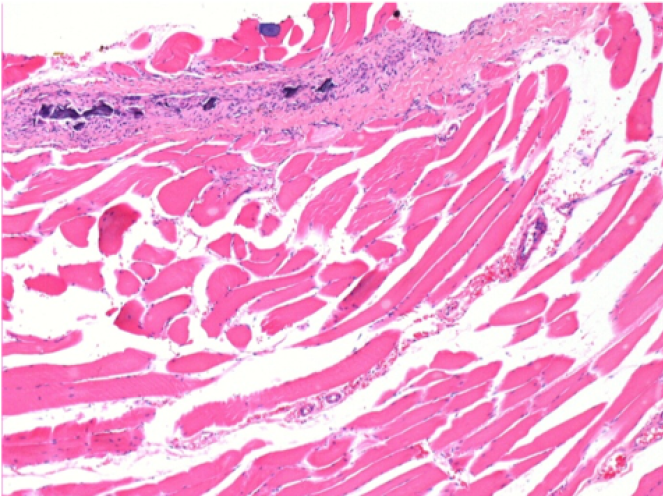

سبعة أشهر بعد حقن إندوبيل

7 أشهر (D210) بعد حقن Endopeel IM 0.1 مل في العضلة أمام الظنبوب اليمنى.

Complete Restitutio ad integrum after 7 months

L : Control-100xD210

R:100xD210

L :Control 50xD210

R50X-D210

يستحث Endopeel انحلال عضلي عضلي قابل للانعكاس الانتقائي ورد فعل التهابي في فترة شهر واحد تقريبًا

- التغييرات العضلية قابلة للانعكاس في مجملها بالكامل تقريبًا

- العضلة هي أفضل مكان لحقن Endopeel بسبب فعاليتها وتحكمها ومدة عملها

- لم يتم العثور على أي نخر أو خراج في جميع أنحاء الدراسة.